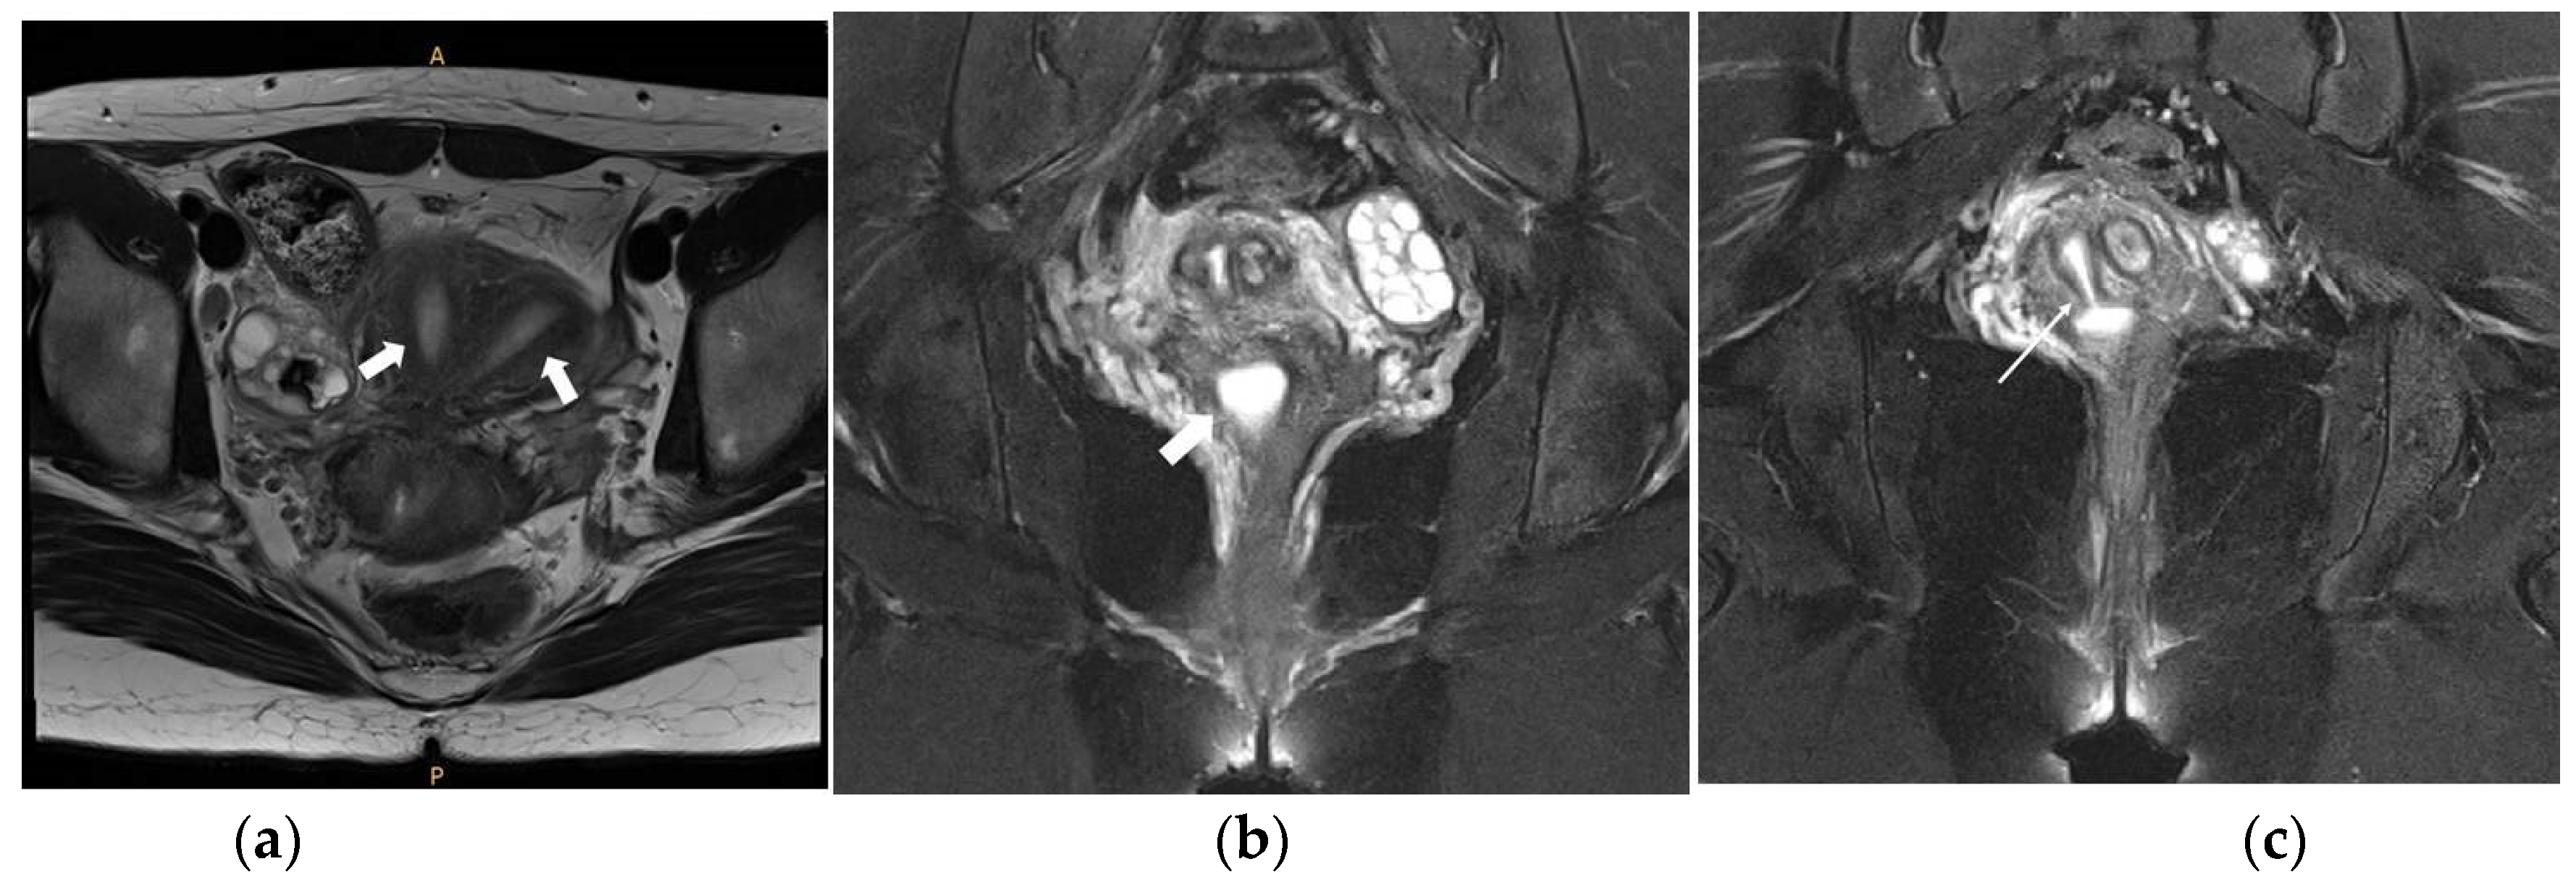

On the abdominopelvic CT image taken at the ER, we noticed she had HWW syndrome (right side hemi-vagina and right kidney agenesis) with acute pyelonephritis (APN) of the left kkidne (Figure 3a,b). After admission, transvaginal USG (Figure 4) and pelvic MRI (Figure 5a–c) were performed. We planned to perform the vaginal wall resection surgery on the next menstrual period as she needed antibiotics treatment for the APN, and the amount of hematocolpos was not so extensive that we could not clearly identify the bulging vaginal wall.

Figure 5.

Pelvic MRI images. (a) Axial view T2-weighted image showing the two uterine corpuses (indicated with two white arrows); (b) Coronal view T2-weighted image showing the small cystic mass filled with fluid suggesting hematocolpos on the right side (indicated with a white arrow); (c) Coronal view T2-weighted image showing the hematocolpos connected with the right endometrial cavity (indicated with a white arrow).